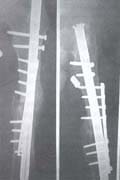

* Figura 3 A-D. Fractura de fémur con clavo bloqueado, distracción del foco de fractura, ruptura de los pernos distales, inestabilidad. Resultado después de colocar placa e injertos óseos.

* Figura 4 A-B. Fractura de fémur con clavo bloqueado no consolidada, tratamiento y consolidación con placa e injertos óseos.